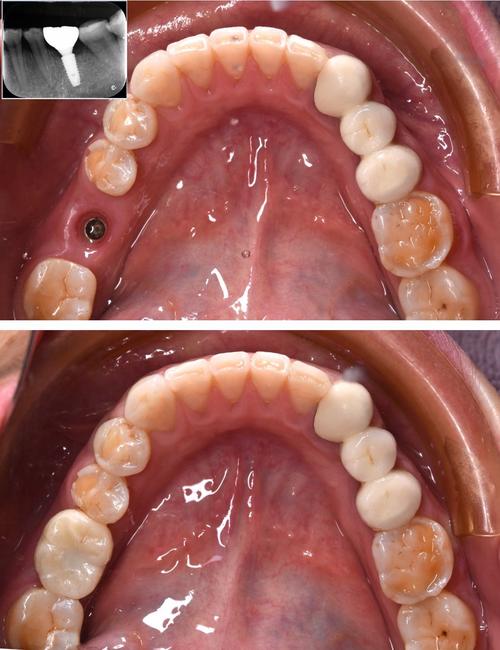

| 种植体植入 | 按照术前设计方向植入种植体,扭矩需≥35Ncm(确保初期稳定性);植入后拍摄CBCT确认位置。 | 避免穿通牙槽骨侧壁,下颌后牙区需远离下牙槽神经管(距离≥2mm)。 |

| 临时修复 | 对符合条件的患者,安装临时牙冠,调整咬合避免早接触;无法即刻负重者可缝合牙龈。 | 临时牙冠需降低咬合高度,防止种植体承受过大咬合力。 |